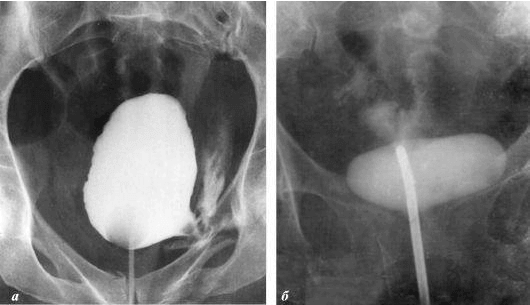

Je vais vous montrer quelques photos pour illustrer ce qui se passe dans le système génito-urinaire et les autres organes d'un homme qui ne pratique pas l'activité sexuelle.

interesting image

À quoi ressemble l'inflammation de la prostate causée par la stase du sperme (lorsque les testicules ne se vident pas). L'inflammation constante conduit d'abord à l'adénome de la prostate, puis au cancer. C'est une conséquence inévitable de la prostatite, raison pour laquelle on l'appelle « la maladie des seniors».